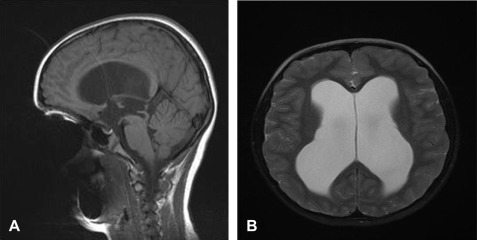

Dandy Walker malformation

agenesis/hypoplasia of cerebellar vermis resulting in cystic enlargement of 4th ventricle

can exist with or without hydrocephalus

can be hypotonic & ataxic